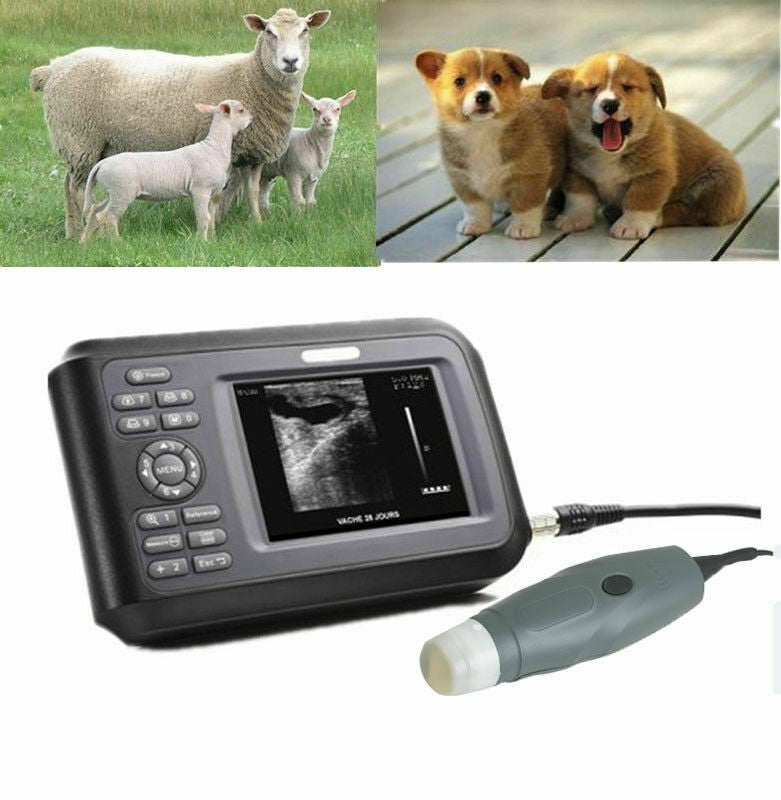

Veterinary Vet Ultrasound Scanner Machine System Kit For Pregnancy Animal Use

The Veterinary Vet Ultrasound Scanner Machine System Kit for Pregnancy Animal Use is a specialized diagnostic tool designed to monitor the health and development of animals during pregnancy. This portable and user-friendly ultrasound system is ideal for veterinarians, farmers, and animal clinics, enabling quick and accurate pregnancy detection and monitoring in a variety of animal species, including cattle, sheep, pigs, dogs, and horses.

The system typically comes with a probe that is specifically designed to provide clear imaging of the animal’s reproductive organs, allowing the veterinarian to determine the pregnancy status, number of fetuses, and their development stages. With real-time imaging and high-resolution capabilities, it helps in assessing the health of the fetus and identifying potential complications. The machine is lightweight and portable, making it easy to use on farms or in field environments. This ultrasound system is a valuable tool for ensuring the health and wellbeing of pregnant animals and managing breeding programs efficiently.